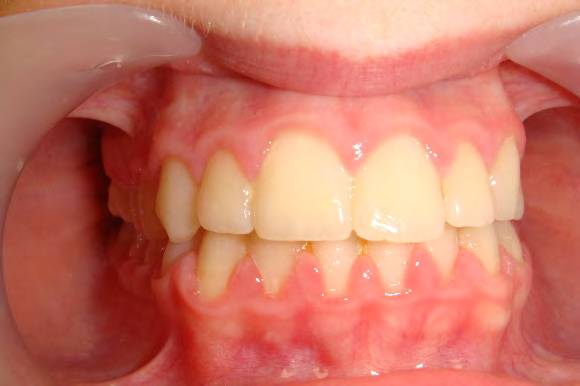

Below are cases treated at Vakresmil without extractions within the last three years. The families had been told, “It is simply not possible for your child to be treated without extractions” by orthodontists. Judge for yourself if that was right or wrong.

The overall aim is to produce the best smile we can — a “beautiful smile”, if you will — without premolar extractions, headgear, facemasks or banded appliances. A smile that both the patient and we at Vakresmil can be proud of.